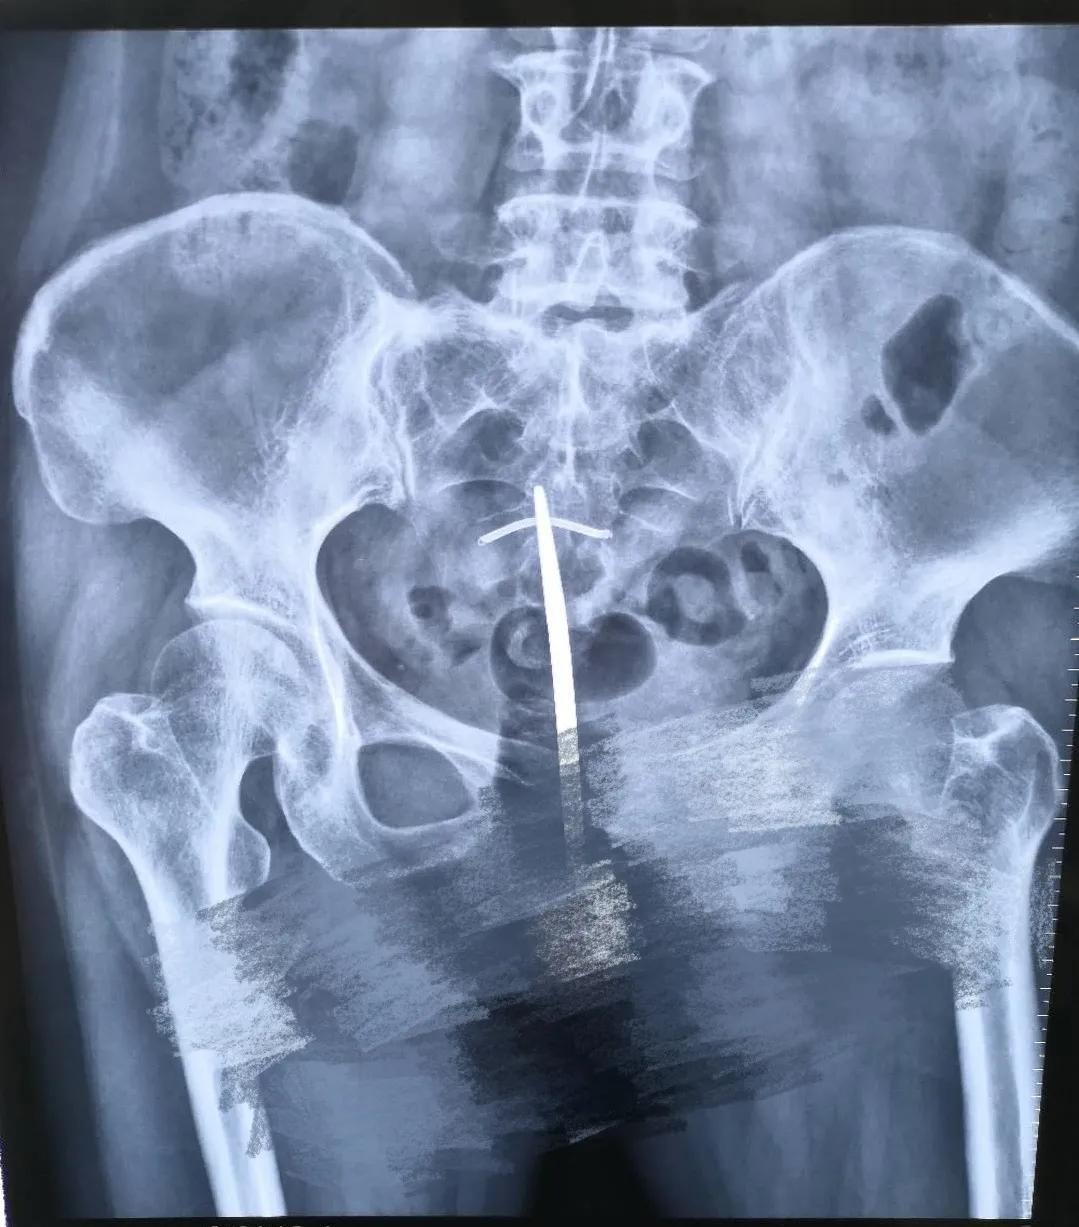

术前经过精细检查,结合超声和定位X线平片,我们判断残留节育器约3厘米,嵌顿于子宫肌层内,科室讨论后决定手术方式为经宫腔镜节育器取出备腹腔镜监视。由安医二附院专家范懿隽主任及王青元医生亲自主持宫腔镜检查+镜下残余节育器取出术。宫腔镜下见近宫腔中段处可见一实性隔样组织将宫腔分为上下两部分,宫腔内外全不可见外露的金属,这种情况下常规盲操作是无法探及节育器的。置入宫腔镜专用剪刀,直径仅0.5毫米,剪开覆盖于金属环表面的内膜组织,见断裂金属环,两端深深插入两侧壁肌壁间,同时导致宫腔内形成纤维束状粘连。微型剪刀分离两侧壁纤维束状粘及环表面黏膜完全暴露残余环。取环顺利,用时短,术中出血极少,患者及家属非常满意!